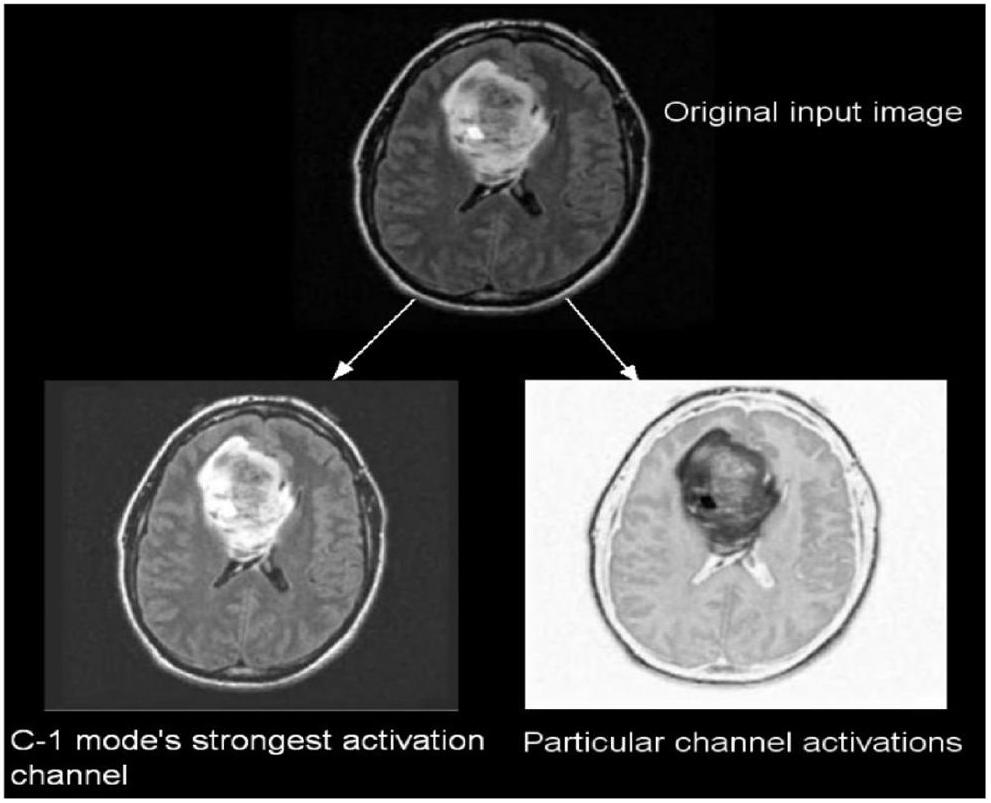

تم أخذ ما مجموعه 299 صورة بشكل عشوائي من مجموعة البيانات لكل فئة، ثم تُستخدم تلك الصور للاختبار. يمكن عرض تنشيطات طبقات الالتفاف في الشبكة العصبية التلافيفية للحصول على رؤية أفضل للميزات.

A total of 299 images are taken randomly from the dataset for each category, and then those images are used for testing. The activations of the CNN’s convolution layers can be displayed for a better view of the features